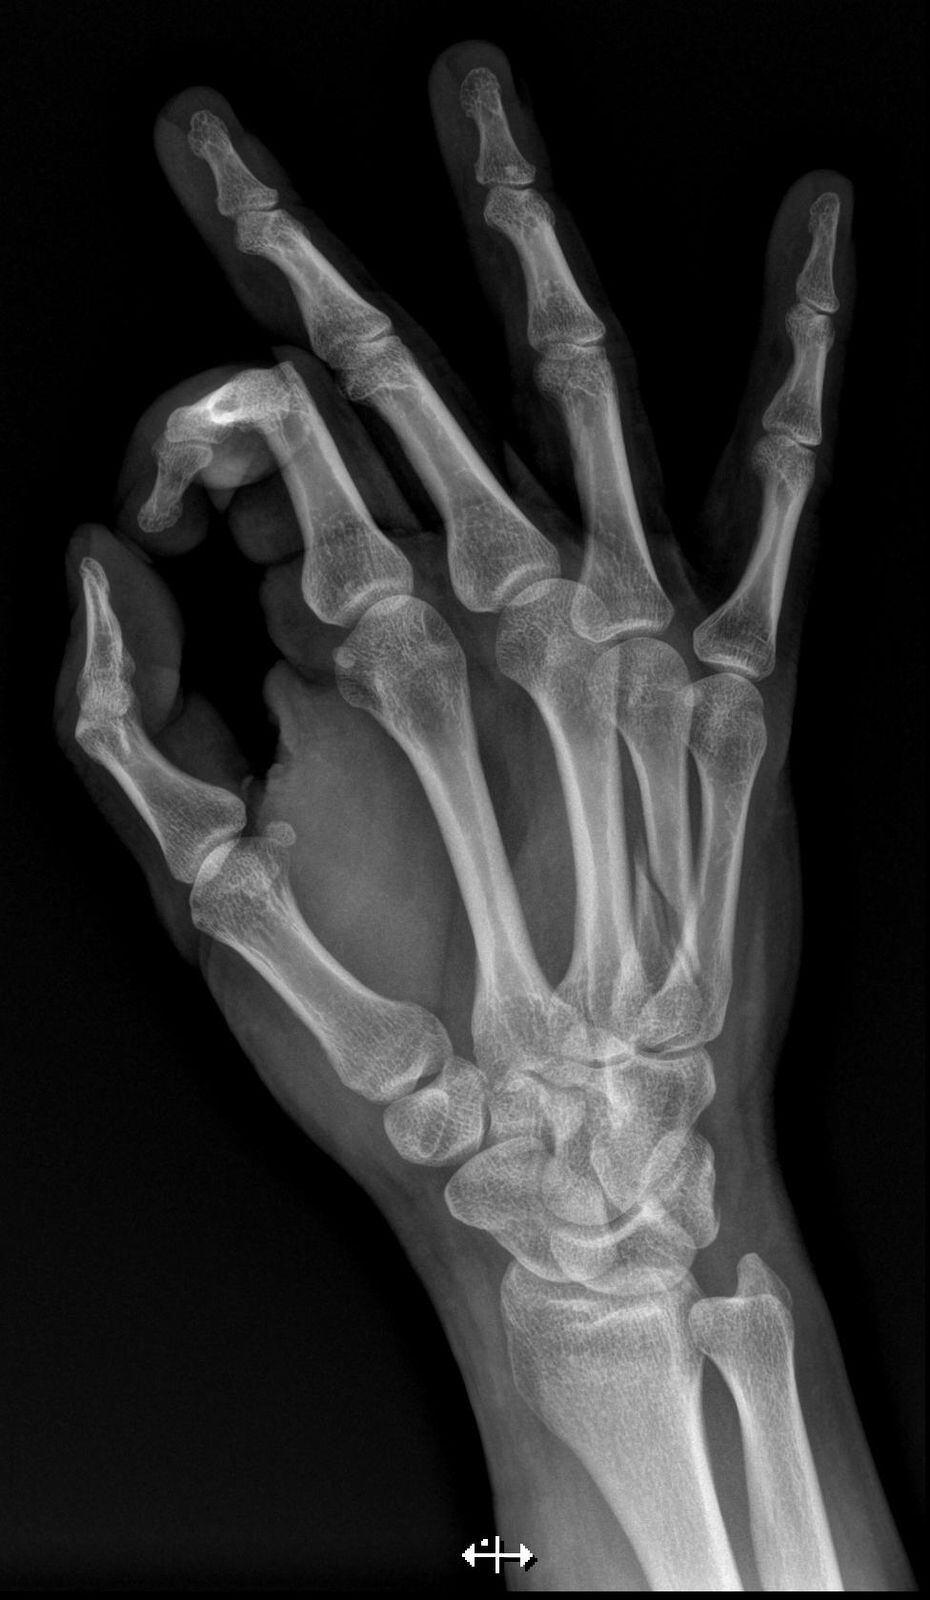

Marvin Ballestero, reconocido locutor del programa Pelando el Ojo, se refirió a lo complicado que ha sido recuperarse de una fractura que tuvo en su mano izquierda.

“Tuve un accidente en la casa el pasado 7 de mayo en la noche, hice un movimiento de fuerza y por la movilidad de la mano se me hizo una lesión, una mala fuerza que hice”, le comentó a La Teja en una entrevista.

Ballestero contó que cuando fue a revisarse le pusieron una férula.

“El ortopedista dice que hay dos opciones: la primera que solde el hueso, y la segunda que tenga que ir a una operación para que el hueso metacarpiano se pegue con unos pines y ver cómo queda con el tema de la movilidad”, dijo.